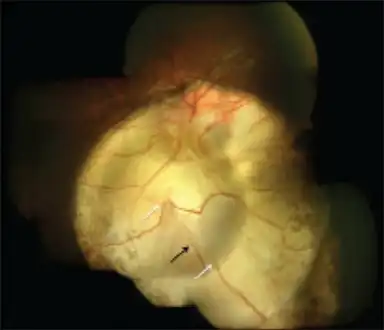

| Coloboma in a 16-year-old female | |

Typically a coloboma appears oval- or comet-shaped with round end towards the centre. There may be a few vessels (retinal or choroidal) at the edges. The surface may have irregular depression.

Right fundus with small coloboma at the inferior edge of the nerve that is vertically elongated. -

Type 5 disc involvement in coloboma of choroid-left eye